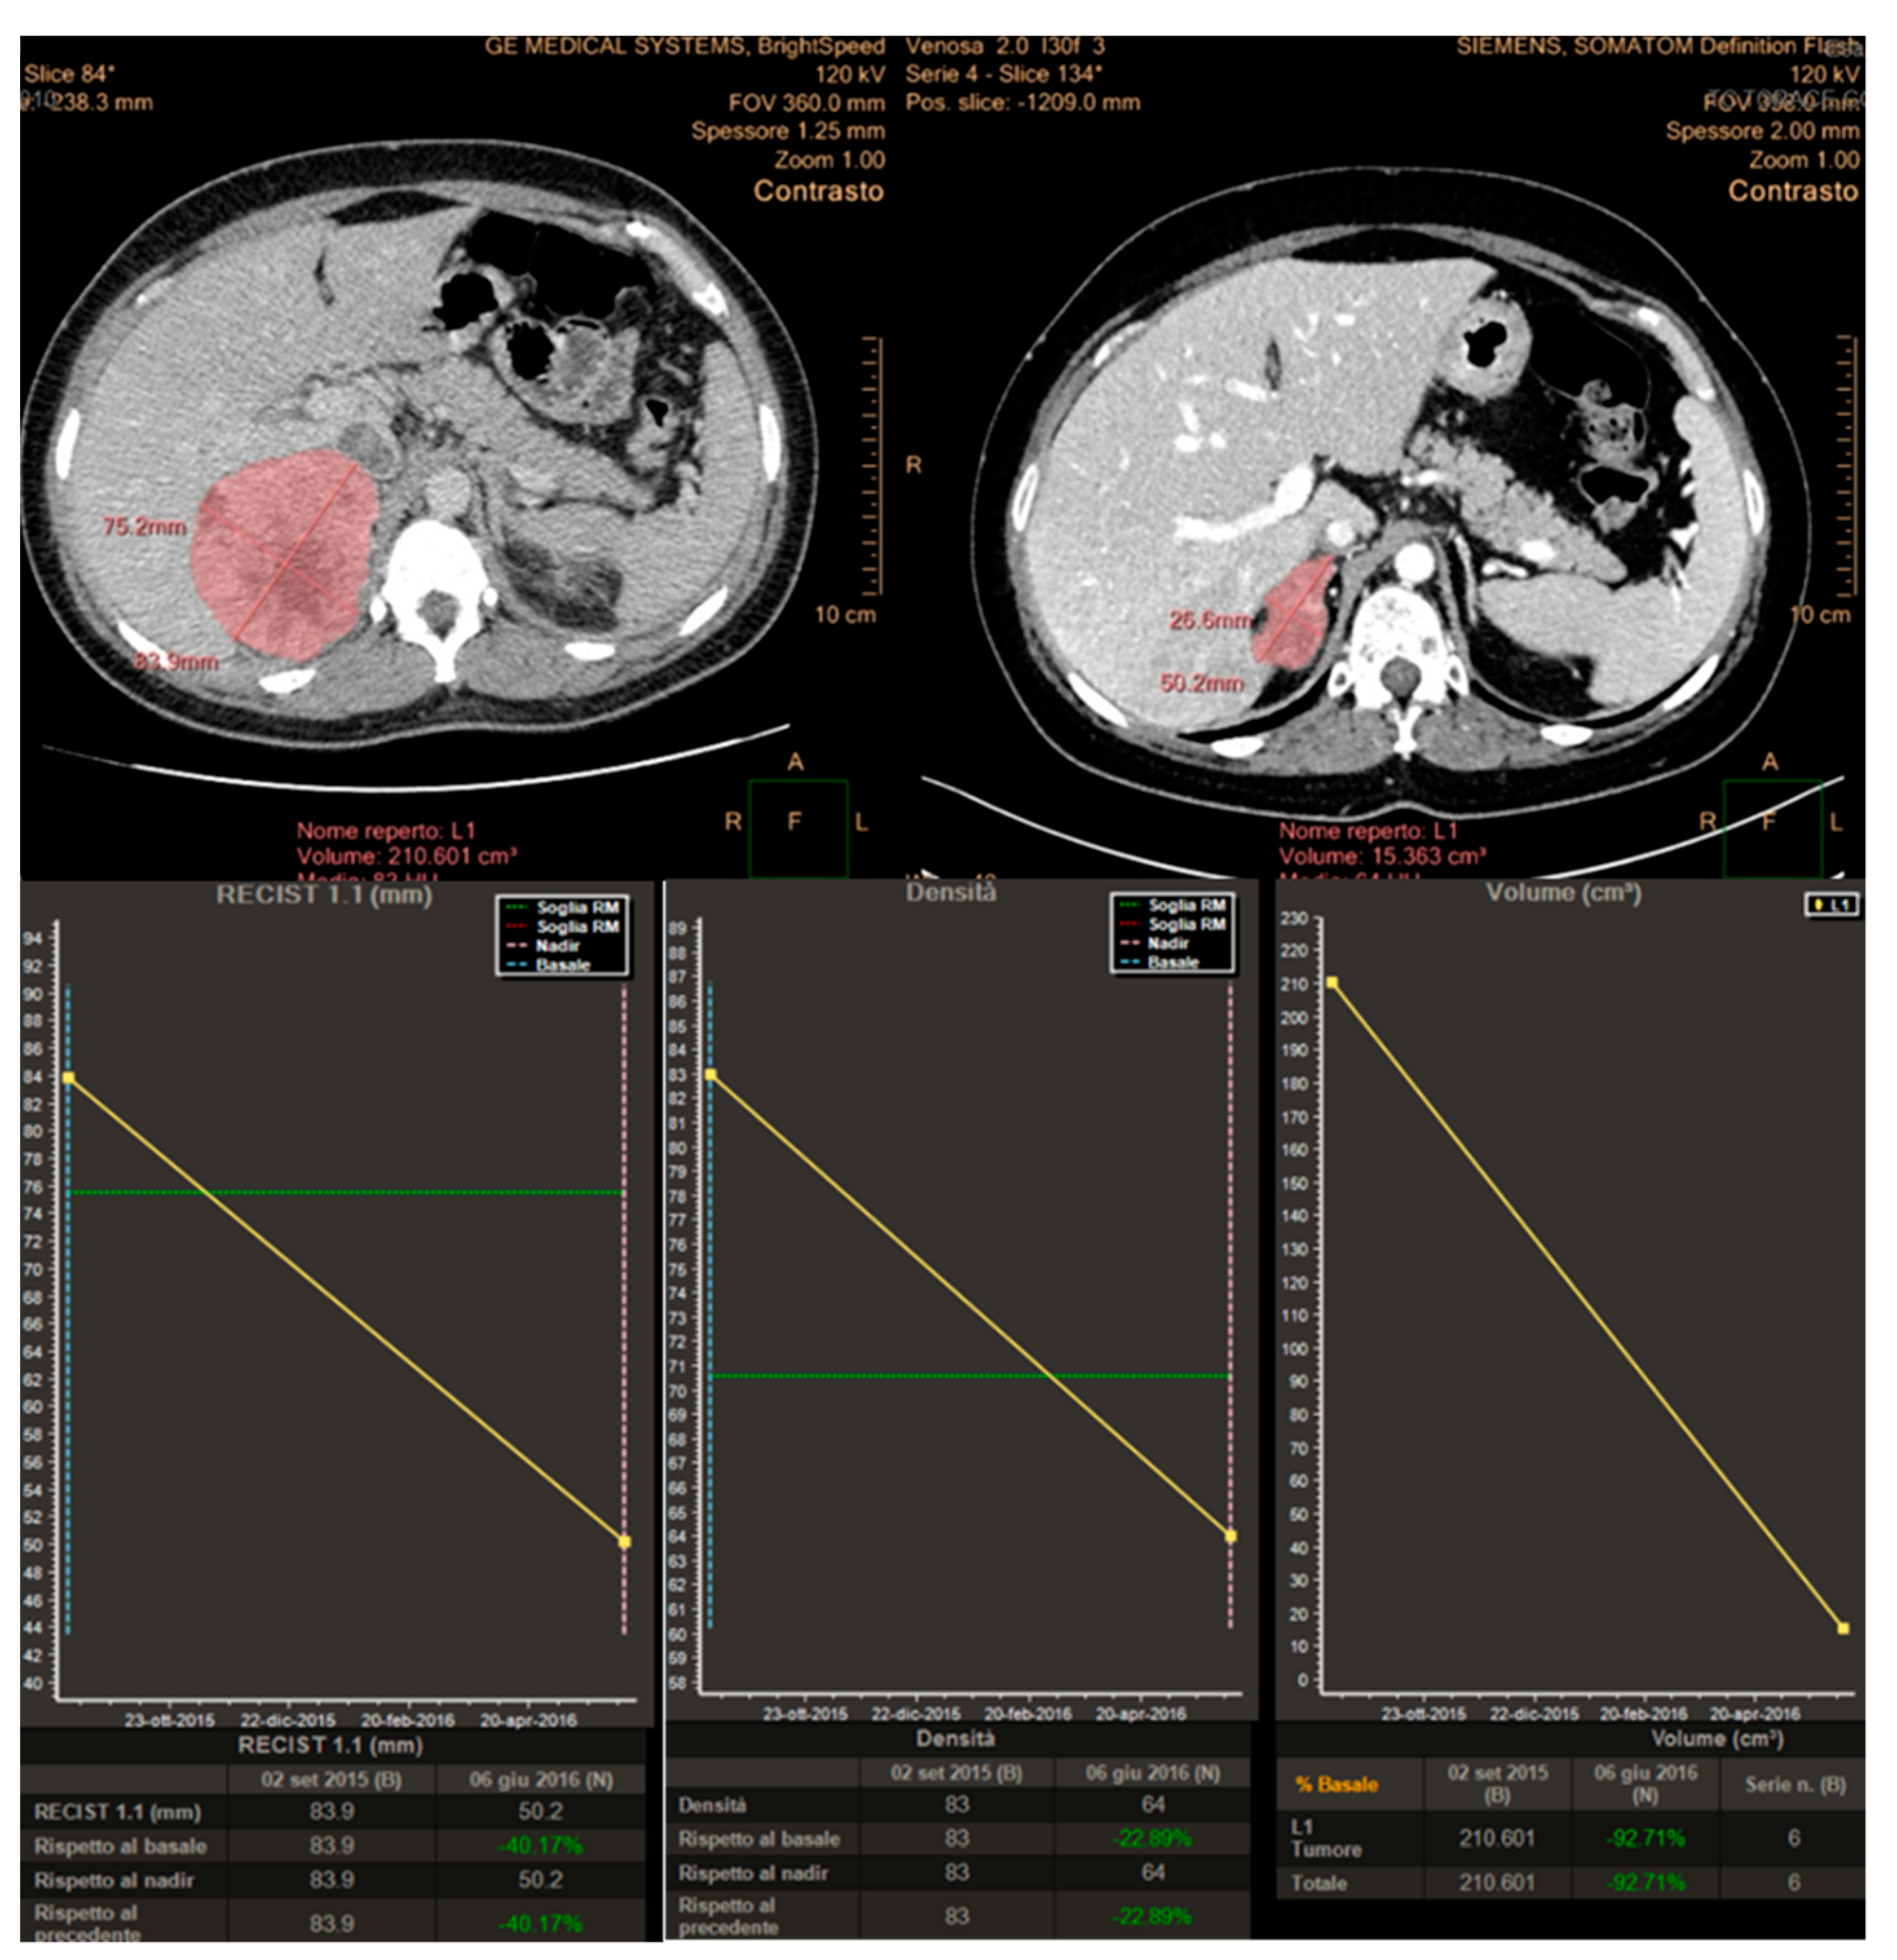

Finally, 10 patients (29.4%) considered responsive by the volumetric criteria were not confirmed by Choi in 1 patient (2.9%) and RECIST 1.1 in another patient (2.9%). An example of a large pelvic secondary implant, considered as a PR using the Choi criteria, otherwise classified as PD when applying RECIST 1.1 and volumetric criteria is shown in Figure 1.

Figure 1. Disagreement in response assessment within the three criteria: according to Choi, the decrease in tumor attenuation was evaluated as a partial response, while according to both Volume and RECIST 1.1 its increase in planar dimensions and volume resulted in Progressive Disease.

Imaging has a pivotal role in objectively defining tumor response or progression of cancer patients during systemic therapy. RECIST criteria, introduced in 2000 [20], are the most standardized, scientifically accepted and currently used system for tumor response evaluation. As mentioned in the introduction, these criteria, even after their revision [14], have several limitations linked to the heterogeneity of the forms and contours of tumor lesions and among different lesions in the same patient. These limitations can be addressed at least in part by the concomitant use of others response criteria. In patients affected by GIST, treated with the tyrosine kinase inhibitor imatinib, Choi criteria demonstrated that the degree of contrast enhancement at CT reflects vascular and interstitial volumes of the tumor, providing information about its structure and biological behavior, even in the absence of size variations [21,22]. In addition, the introduction in clinical radiology of dedicated software allows a fast and semiautomatic segmentation of the analyzed lesions with the automatic measurements of diameters as well as volume and attenuation changes. This approach aims to reduce the subjectivity of the analysis and to detect earlier subtle variations during and after systemic antineoplastic therapy, as well as to shorten the time spent by the radiologist for the manual tumor analysis, while increasing the reproducibility of the evaluation (Figure 1).